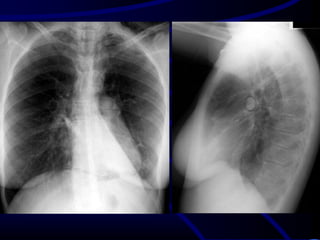

A 27-year-old man is referred to you for evaluation of an

abnormal chest radiograph. About 5 months ago, he consulted

a doctor because of excessive thirst. Evaluation resulted in the

diagnosis of diabetes insipidus, which responded favorably to

desmopressin administered nasally. Recently, he started to

notice shortness of breath when climbing stairs, and a chest

radiograph was obtained.

•Patient history reveals significant tobacco smoking, up to two

packs daily, for at least 14 years. The patient noticed the

shortness of breath for at least 2 years, and recently, he noted

a point of tenderness over the chest wall, lateral to the

posterior axillary line on the left.

•Oxygen saturation is 94% while breathing room air, and the

rest of his vital signs were normal. Auscultation reveals only

rare crackles without prolongation of the expiratory phase.

There is a point of tenderness over the left sixth and seventh

ribs in the posterior axillary line, and a chest CT scan is

obtained.